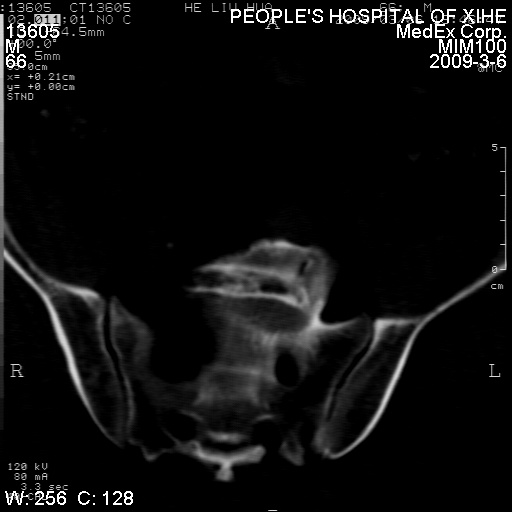

标题: CT18522:男,66岁。考虑结核有错吗 [打印本页]

标题: CT18522:男,66岁。考虑结核有错吗

x线片示:骶骨密度增高。

考虑----腰椎骶化-----退变-----椎管狭窄

腰骶椎退行性改变。

退行性变,椎体滑脱

腰椎滑脱并有退变

退行性变,椎体滑脱。建议同椎体平行进一步扫描。